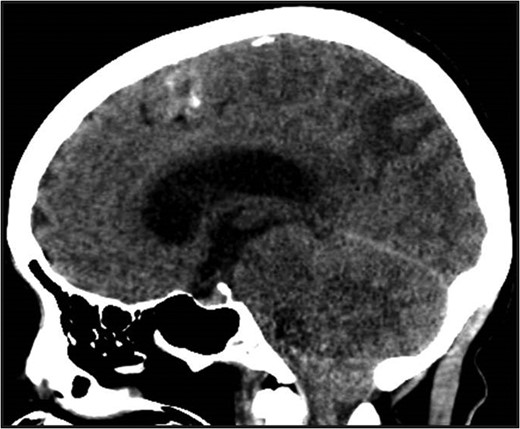

MRI brain at the time of diagnosis, Axial T2 sequence. Vasogenic edema involving the bilateral cerebral hemispheres, with relative sparing of the frontal lobes suggestive of PRES. Pneumocephalus is present secondary to interval placement of an external ventricular drain (seen in the right lateral ventricle).